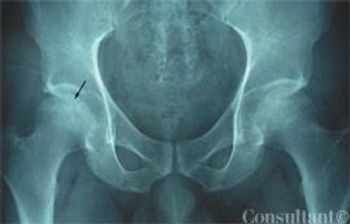

Ankylosing spondylitis involving the symphysis pubis is a rare and very unusual manifestation in male and females. Herein, we present a case of a 43-year-old female with ankylosing spondylitis involving the symphysis pubis.

Does the lupus patient have comorbid age-related osteoarthritis? Is it iliopsoas bursitis or trochanteric pain syndrome? Eight images with reflections on differential diagnosis of hip pain.